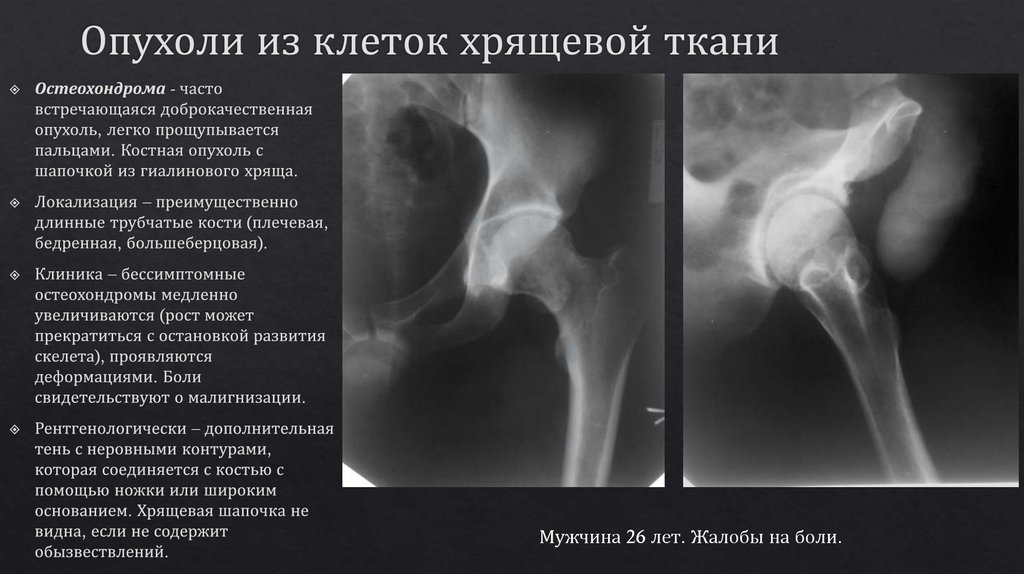

Рентгеновские снимки доброкачественных опухолей костей

Раздел: Моменты озарения